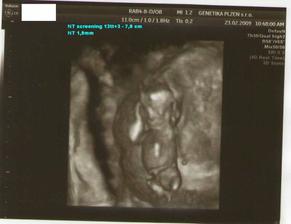

23.2.09 - NT screening I. trimestru Genetika Plzeň

23.2.09 - NT screening I. trimestru na Genetice v Plzni - NT 1,9mm, nosní kůstka přítomna,

mimi má 7,9 cm(CRL), celkem i s nožičkama 12cm, vše OK, placenta vzadu(OK) - komplet výsledek: negativní (hurááááááá)